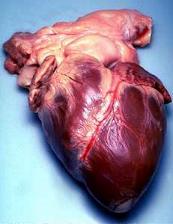

The largest part of the heart is usually slightly offset to the left side of the chest (though occasionally it may be offset to the right) and is felt to be on the left because the left heart is stronger and larger, since it pumps to all body parts. Because the heart is between the lungs, the left lung is smaller than the right lung and has a cardiac notch in its border to accommodate the heart.[7] The heart is cone-shaped, with its base positioned upwards and tapering down to the apex.[7] An adult heart has a mass of 250–350 grams (9–12 oz).[16] The heart is often described as the size of a fist: 12 cm (5 in) in length, 8 cm (3.5 in) wide, and 6 cm (2.5 in) in thickness,[7] although this description is disputed, as the heart is likely to be slightly larger.[17] Well-trained athletes can have much larger hearts due to the effects of exercise on the heart muscle, similar to the response of skeletal muscle.[7]

An anatomical specimen of the heart